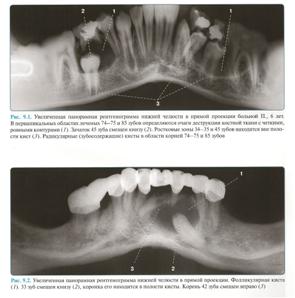

2) Ортопантомограмма.

Позволяет оценить сразу обе челюсти, возможна оценка состояния верхнечелюстных пазух.

Кератокиста распространяется по длиннику челюсти и не приводит к выраженной деформации кости. Поэтому определяют ее при достижении больших размеров. Киста распространяется на тело, угол и ветвь челюсти. Рентгенологическая картина характеризуется наличием обширного разрежения костной ткани с четкими полициклическими контурами, при этом неравномерное рассасывание кости создает впечатление многокамерности. Нередко в процесс вовлекаются венечный и мыщелковый отростки. Кортикальная пластинка истончается и иногда на некоторых участках отсутствует. На рентгенограмме обычно определяется периодонтальная щель корней зубов, проецирующихся на область кисты (рис. 3). Первичную одонтогенную кисту диагностируют на основе характерных клинико-рентгенологических проявлений. Ее следует дифференцировать от амелобластомы. При последней наблюдается выраженное вздутие челюсти. Окончательный диагноз устанавливают после морфологического исследования биопсийного материала. Проводится открытая биопсия с обязательным иссечением костной ткани и оболочки ее кисты по типу цистотомии. Биопсия одновременно является первым этапом хирургического лечения кисты. Макроскопическипервичная одонтогенная киста представляет единую полость с бухтообразными вдавлениями в окружающую кость, покрытую оболочкой и выполненную аморфной массой грязно-белого цвета. Микроскопически она характеризуется тонкой фиброзной капсулой, выстланной ороговевающим многослойным плоским эпителием. Лечение хирургическое. Так как киста способна к рецидивированию и озлокачествлению, показано при сохранении костных стенок полное удаление ее оболочки. В других случаях применяют двухэтапный метод операции.

Фолликулярная киста

Эта киста развивается из эмалевого органа непрорезавшегося зуба, преимущественно третьего большого коренного на нижней челюсти, клыка и третьего большого коренного зуба на верхней челюсти. Клинические симптомы фолликулярной кисты сходны с проявлениями других кист челюстей, однако при осмотре зубов характерно отсутствие одного из них в области локализации кисты, за исключением случая образования ее от сверхкомплектного зуба. Отмечена возможность развития амелобластомы из фолликулярной кисты. Рентгенологически определяют разрежение костной ткани с четкими ровными границами по типу монокистозного очага и наличие ретенированного сформированного зуба, коронка которого либо обращена в полость кисты, либо прилегает к ее стенке. Фолликулярную кисту необходимо дифференцировать от амелобластомы и первичной одонтогенной кисты. Макроскопически определяется однокамерная полость, выстланная оболочкой и содержащая желтоватую прозрачную жидкость с кристаллами холестерина. Микроскопически оболочка кисты представлена тонким слоем соединительной ткани, покрытым многослойным плоским эпителием, толщиной в 2–3 клетки. Лечение заключается в цистэктомии с удалением ретенированного зуба или в двухэтапной операции.